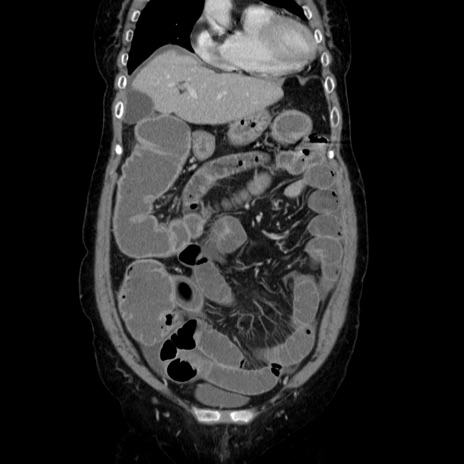

症例5(冠状断像)

【症例】70歳代女性

【主訴】お腹が張る

【現病歴】1週間くらい前から腹部膨満の自覚あり。昨日夜から増悪したため、本日救急外来受診。

【身体所見】意識清明、BT 36.5℃、BP 165/106mmHg、HR 80bpm、SpO2 98%、腹部:膨満、軟、自発痛・圧痛なし、触診にて不快感あり、腸蠕動音:減弱

【データ】WBC 12600、CRP 1.04